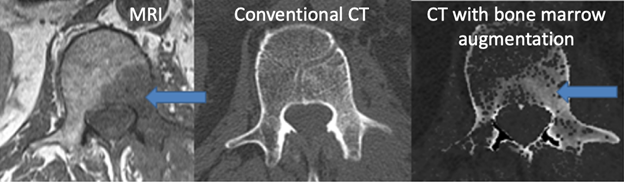

Enhanced CT visualization of pathology

PI: Joshua Polster, MD

We have developed post-processing techniques to enhance detection of bone marrow lesions and also soft tissue lesions using conventional single-energy CT data. For bone marrow lesion detection, a post-processing algorithm was created to enhance the soft tissue components of bone.  The technique has been preliminarily tested in clinical cases of MRI proven, CT-occult bone marrow lesions of the lumbar spine, demonstrating detection of lesions in 8 of 11 CT-occult lesions. For soft tissue lesion detection, a fluid-sensitive look-up table was created to mimic STIR MRI imaging with single-energy CT data.  A steak model has been evaluated with blinded independent reading from 4 musculoskeletal radiologists demonstrating the detectability of injected lesions in skeletal muscle, demonstrating excellent accuracy of lesion detection using this technique.